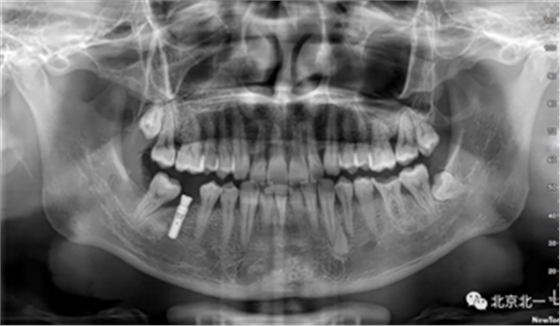

第一步:术中微创种植, 穿龈愈合。

第二步:拔牙

术后拍片。